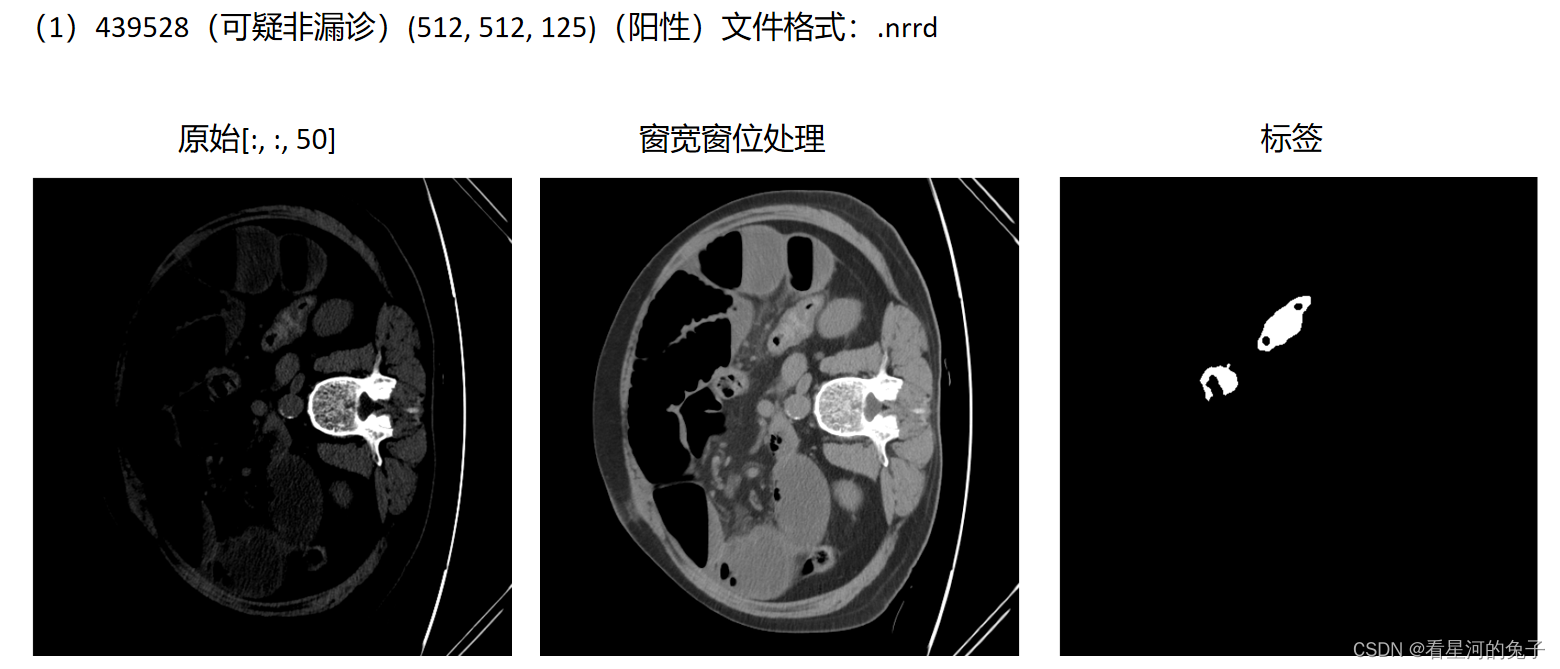

结果展示